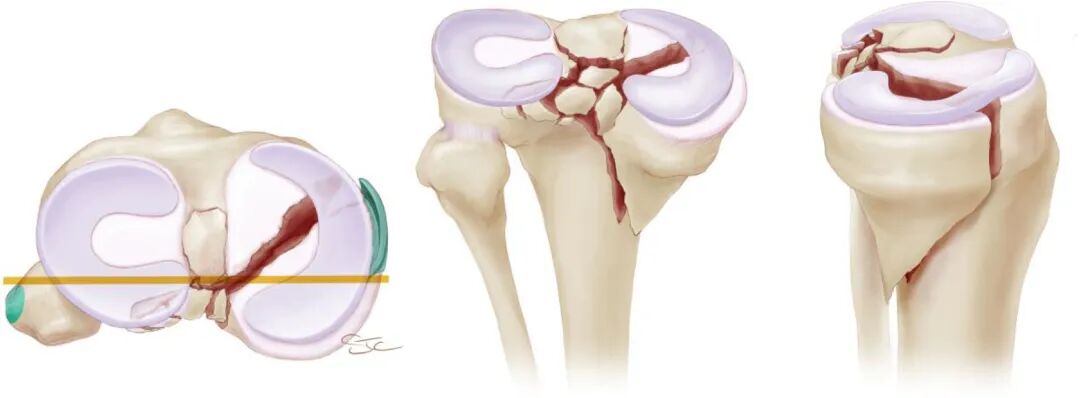

胫骨平台关节面的复位要求还与骨折关节面所处区域有关,对于核心负重区[即膝关节在完成日常运动(如步行和中等强度跑步)过程中,胫骨平台的主要承重区域]的关节面骨折,应当力求手术解剖复位;而对于非核心负重区的骨折,则可适当放宽复位要求,甚至可采取保守治疗。

维持膝关节稳定性对于胫骨平台骨折复位至关重要;特别是对于关节面严重粉碎塌陷的骨折,很难实现关节面的解剖复位,这时最重要的目标莫过于恢复膝关节的稳定性,允许患者术后在相对无痛的情况下尽早开始康复训练, 随着时间的推移,患者膝关节可能会因为残留的关节面不平整而出现PTOA,但这一般是数年或数十年以后的并发症;若骨折术后膝关节不稳定,患者会因难以开始康复锻炼进而导致膝关节疼痛、活动受限和打软腿等。

胫骨平台骨折术后膝关节不稳定,既可能因为关节面复位不良使相应关节间隙增大所致,也可能因为骨折合并膝关节韧带断裂或韧带止点撕脱性骨折引起的韧带性不稳定所致。

在重建胫骨平台骨折术后膝关节稳定性时,除了要做到关节面复位满意之外,还要兼顾对前交叉韧带体部断裂或止点处骨折的处理。